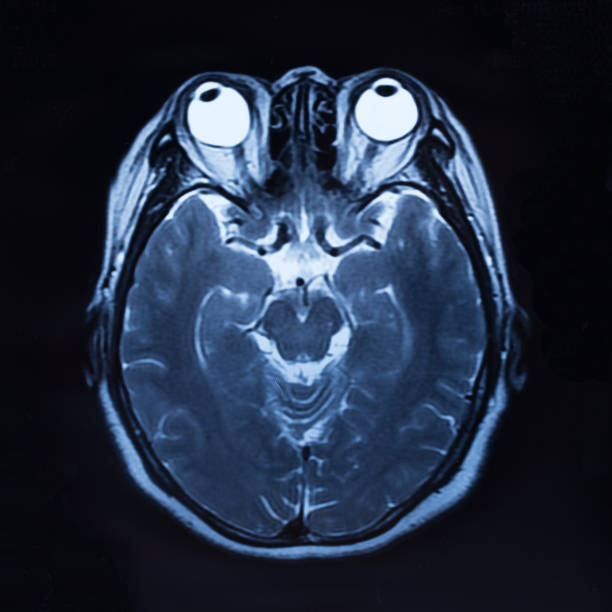

뇌출혈 전조증상 세 번째는 시력과 균형감각의 상실을 이야기 할 수 있습니다. 뇌 혈관 문제로 생기는 뇌출혈은 시신경과 관련하여 시야가 흐려지고 눈을 정상적으로 뜨기 어렵기 때문에 시력을 이부 상실할 수 있으며 균형 감각도 둔해져 가만히 있더라도 몸이 계속 기울어져 넘어질 수 있습니다.

또한, 사지의 움직임에 비정상적인 운동신경을 일으켜 정상적인 기능을 할 수 없게 하는 편마비가 있으며, 심하면 사지마비가 옵니다. 언어의 중심에 문제가 있는 언어에 문제가 있어 말하기나 이해에 어려움을 일으키고 의사소통에 어려움을 겪을 수 있습니다. 그리고 후두엽에 뇌졸중이 생겼다면 시력 문제가 발생하기 때문에 시력에 문제가 이어질 수 있습니다.